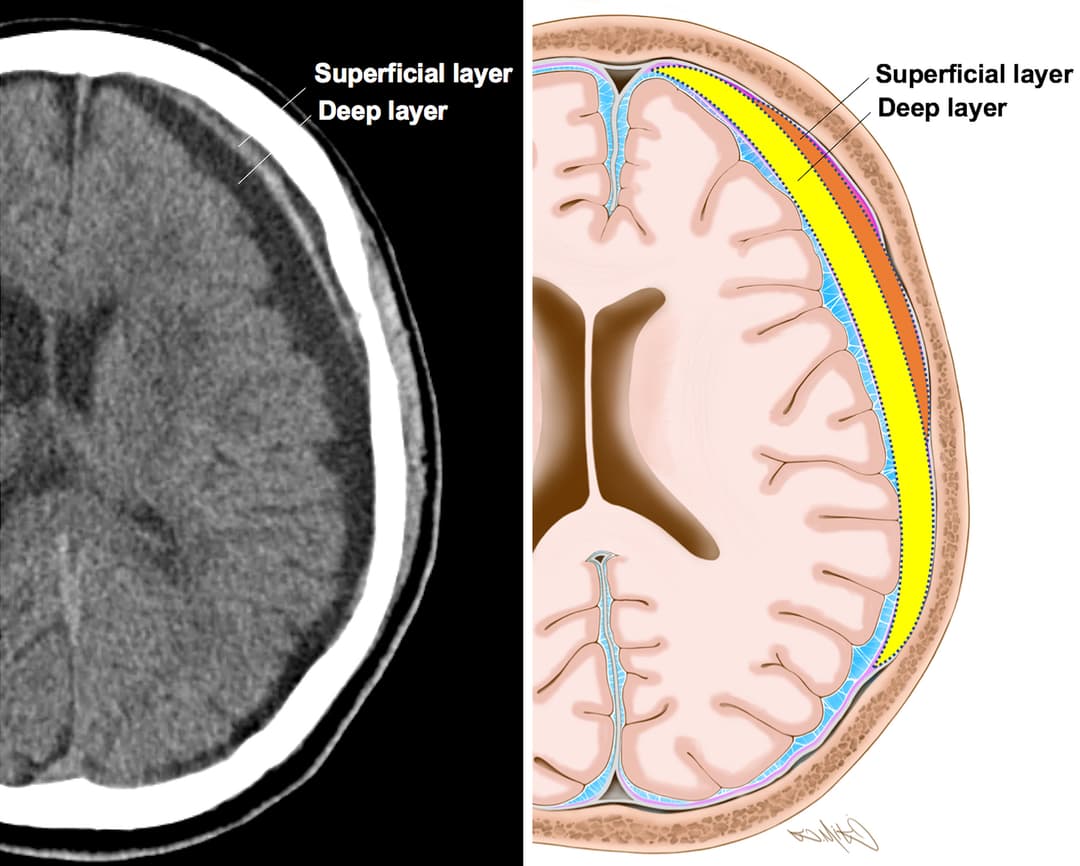

النزف تحت الجافية: الأسباب والأعراض والتشخيص والعلاج

9 ديسمبر ، 2019